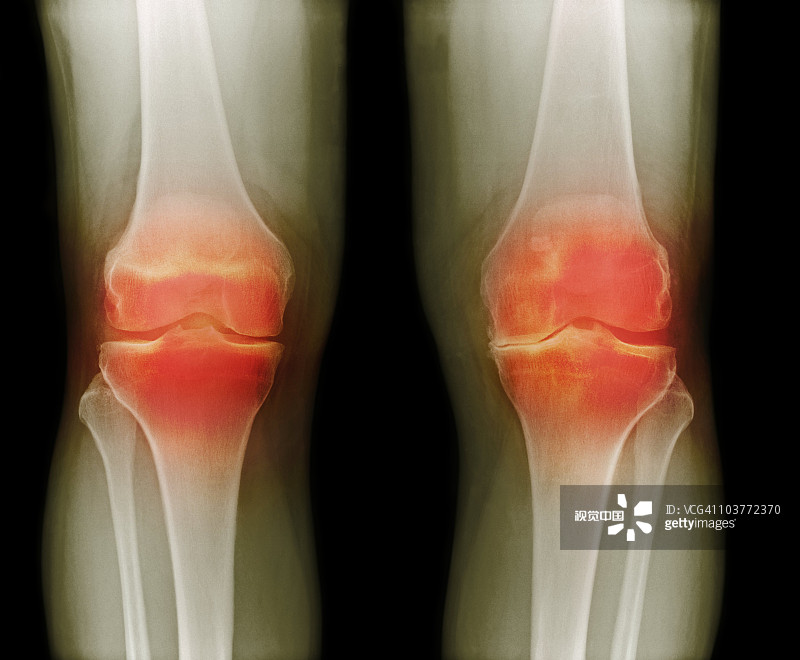

適應(yīng)癥:膝骨關(guān)節(jié)炎

貴醫(yī)附院 | 人臍帶間充質(zhì)干細(xì)胞治療膝骨關(guān)節(jié)炎患者的1期臨床試驗(yàn)

- 2.依據(jù)參考中華醫(yī)學(xué)會(huì)骨科學(xué)分會(huì)關(guān)節(jié)外科學(xué)組制定的“骨關(guān)節(jié)炎診療指南(2018年版)”,明確診斷為膝骨關(guān)節(jié)炎(KOA)